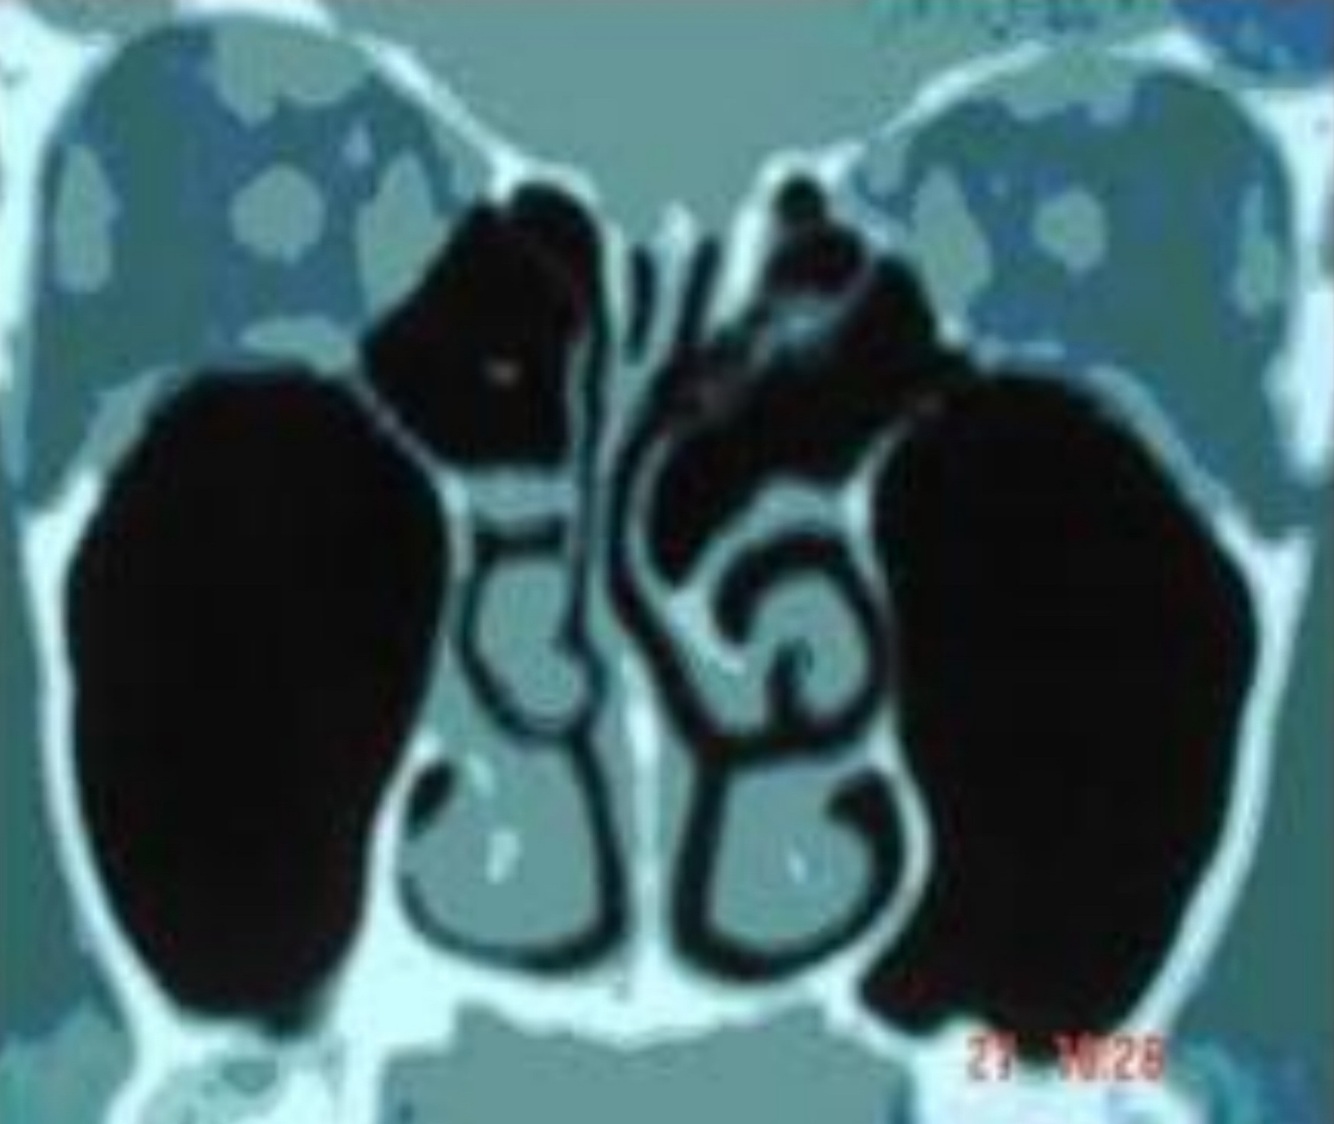

Q

Concha media bulosa